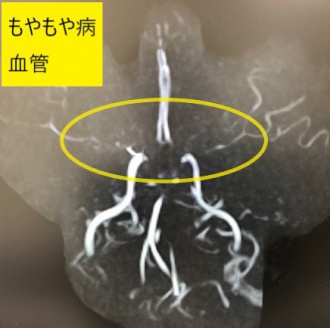

もやもや病とは脳の血管に生じる病気です。内頚動脈という太い脳血管の終末部が細くなり、脳の血液不足が起こりやすくなります。このため、一時的な手足の麻痺、言語障害を起こします。血流不足を補うために、細い異常血管がたくさん発達して血液を送るようになります。この細いたくさんの血管がもやもやとして見えることから、もやもや病という名前がつきました。